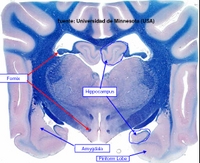

El Sistema Límbico comprende a estructuras de la corteza cerebral que bordean el tronco encefálico, junto a ciertos componentes del hipotálamo, tálamo y epitálamo, y está relacionado con la percepción de las emociones de importancia para la supervivencia del animal, como la defensa, alimentación, escape, etc.. y emociones asociadas con la supervivencia de la especie, tales como la defensa territorial, cortejo, apareamiento, etc.., estando además relacionado con procesos relativos al aprendizaje y memoria.

HIPOCAMPO: Es una estructura de la corteza cerebral con 3 capas de células, llamada ARQUEOCORTEX, de importancia en aprendizaje asociativo y memoria (particularmente memoria de corto tiempo). Tanto pacientes amnésicos como animales con daños en hipocampo exhiben problemas tiempo-dependientes en tareas de comportamiento generalmente descritas como asociativas o relacionadas por naturaleza. Este área del cerebro tiene un bajo umbral de ataques o convulsiones.

AMIGDALA: Es una región altamente diferenciada cerca del polo temporal de los hemisferios cerebrales de los mamíferos. Es un núcleo basal que está implicado en la emoción, memoria, comportamiento social, comportamiento reproductor, miedo y agresión, y modulación de sistemas autonómicos y neuroendocrinos. Muchos de sus efectos son opuestos a los del septum. Lesiones de la amígdala pueden suponer comportamiento dócil, mientras que su estimulación produce comportamiento agresivo.